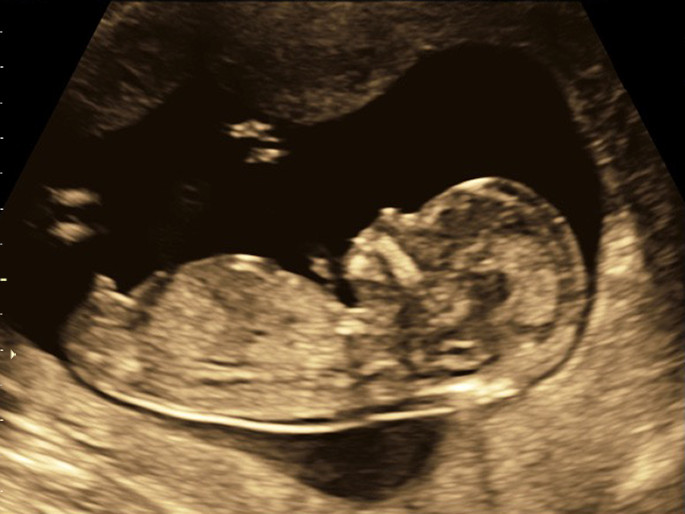

Im Rahmen des Ersttrimesterultraschalls, welcher von 12+0 bis 13+6 Schwangerschaftswochen durchgeführt wird, beurteilen wir die Anzahl der Kinder und ob das Kind / die Kinder wohlauf sind. Außerdem können wir den Geburtstermin anhand der Messung der Länge des Kindes bestätigen oder korrigieren. Einige Fehlbildungen können schon in diesen Schwangerschaftswochen erkannt oder ausgeschlossen werden.

Zusätzlich kann bereits zu diesem sehr frühen Zeitpunkt eine möglichst umfassende Darstellung der körperlichen Entwicklung des Kindes und somit eine frühe Feindiagnostik (Organultraschall) erfolgen.

Diese Untersuchung wird vielfach als die sogenannte „Feindiagnostik“ bezeichnet. Per Ultraschall wird die gesamte Schwangerschaft eingehend untersucht und damit etwa 90% der klinisch bedeutsamen Anomalien entdeckt. Ebenso ist es möglich über eine Blutflussuntersuchung (Doppler) die Funktion der Placenta (Mutterkuchen) zu prüfen. Das fetale Herz ist zu diesem Zeitpunkt meist besonders gut zu untersuchen und es wird eine 85-90%ige Entdeckungsrate relevanter Herzfehler erreicht. Sollten sich hierbei Hinweise für einen Chromosomendefekt oder anderer genetisch bedingter Erkrankungen ergeben, könnte dann zu einem späteren Zeitpunkt durch eine invasive Diagnostik z.B. aus Fruchtwasser, Fetalblut oder Plazentamaterial eine Chromosomenbestimmung vorgenommen werden.